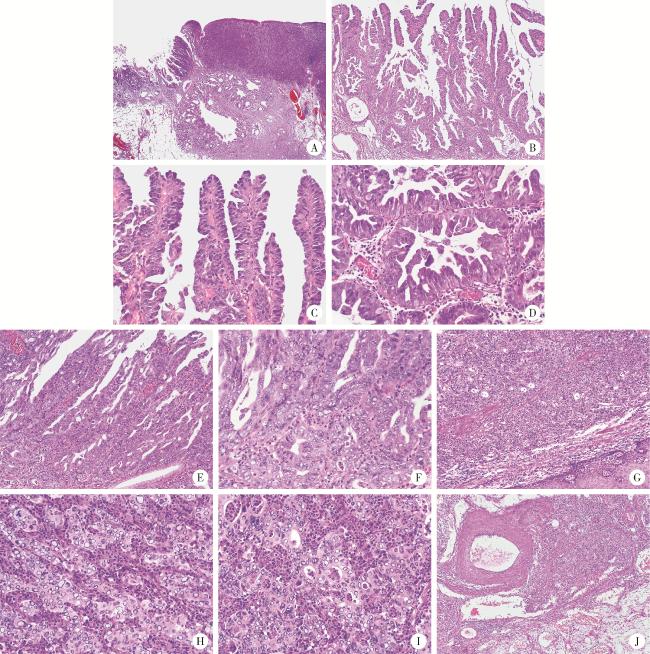

图1 食管胃结合部具有显著空泡状核特征的神经内分泌癌的形态学特征(HE染色)Figure 1 Morphological characteristics of neuroendocrine carcinoma with significantly vacuolar nucleus at the esophagogastric junction (HE staining) A, the hierarchical structure of mucosa and submucosa existed; abnormal branched glands were seen in the tumor area, some were solid, and nodular glands and cystic expansion were seen in the submucosa; B, intramucosal tumor with branching papillary structure; C, D, the surface of the papillary and the glandular was lined with boot-like or cuboidal cells, and a few nuclei were slightly vacuolated; E, F, the lining epithelium of some papillae and glandular cord hyperplasia fused to form a cribriform structure; the nucleus was obviously vacuolated; G, the main body of the tumor is solid, with diffuse arrangement of cells and no involvement of the surface squamous epithelium; H, I, the cells of the solid area were structured with nests, cord, and glandular tubes, with significantly vacuolar changes in nuclei, atypical mitoses, and a large capillary network with a large number of neutrophils in the tumor stroma; J, cancer cell mass seen in submucosa veins. A, 20×; B, G, 100×; C-F, H, I, 400×; J, 40×. HE, hematoxylin and eosin. |